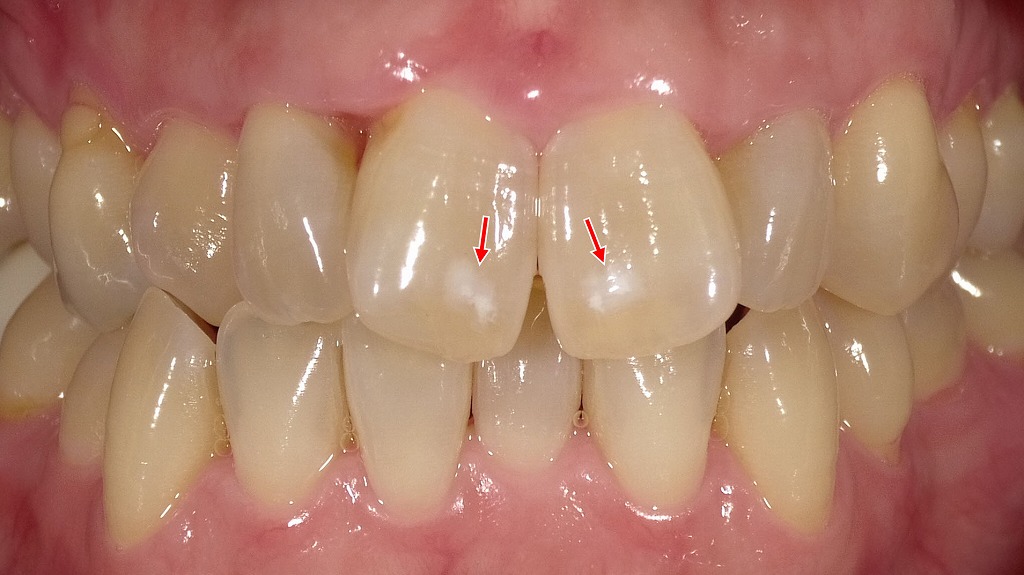

2枚目の画像:ホワイトニング後

2枚目の画像では、ホワイトニング後の状態を示しています。歯全体が明るくトーンアップしており、周囲の色とのコントラストが減少したことで、ホワイトスポットがほとんど目立たなくなっています。ホワイトニングによって歯全体の明度が上がることで、白斑が自然に馴染み、全体として均一な印象に改善されています。

このように、ホワイトスポット自体を「消す」ことはできませんが、ホワイトニングで目立たなくすることは可能です。